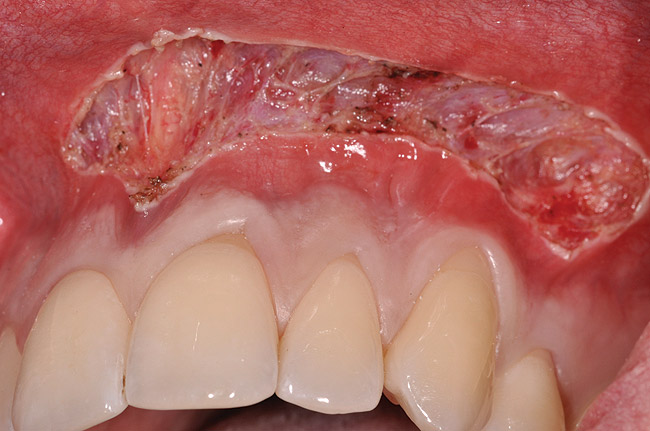

Various procedures to correct deficient gingival contours have been well documented in the dental literature.1,2 Increasing zones of attached gingiva using palatal donor tissue and the free gingival grafting procedure was introduced by Björn almost a half century ago.3 Using palatal donor tissue in the form of a free soft-tissue autograft for root-coverage procedures was reported by Miller.4 Additional procedures were reported using lateral5 or coronal repositioning6-8 of the adjacent attached gingiva via a pedicle flap or the coronal repositioning of previously grafted tissue.9,10 Miller also reported on gingival grafts placed over root surfaces to correct areas of deep-wide gingival recession.11 Further surgical advancements led to the use of subepithelial connective tissue from the palate to obtain root coverage.12-14 Figure 1 shows the pretreatment view of a mandibular central incisor, and Figure 2 depicts the post-treatment view of the site treated with a subepithelial connective tissue graft harvested from the patient’s palatal tissues.

Fig 1. Preoperative clinical view, mandibular central incisor.

Figure 1

Fig 2. Post-treatment clinical view after subepithelial connective tissue graft.

Figure 2